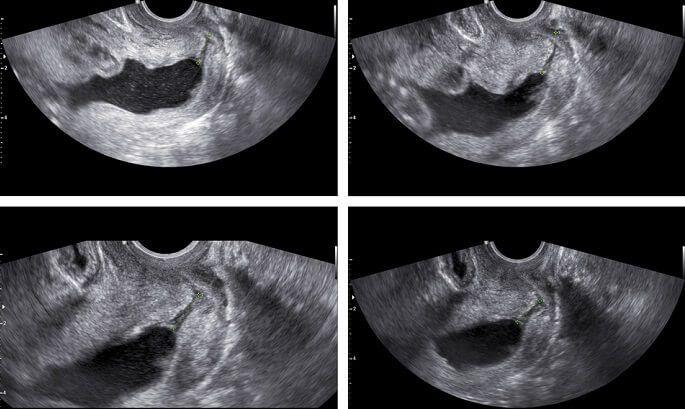

כאשר מאובחנת אי ספיקת צוואר הרחם בטרם הריון, נעשית התפירה בצורה בררנית בשבועות מוקדמים של ההריון (15-12). אם האבחון לא היה מוקדם ואי-הספיקה אובחנה בשל קיצור צוואר הרחם בבדיקת על-שמע במהלך ההריון, ניתן לבצע גם תפירת צוואר מאוחרת, אולם סיכוייה של זו להצליח קטנים יותר.